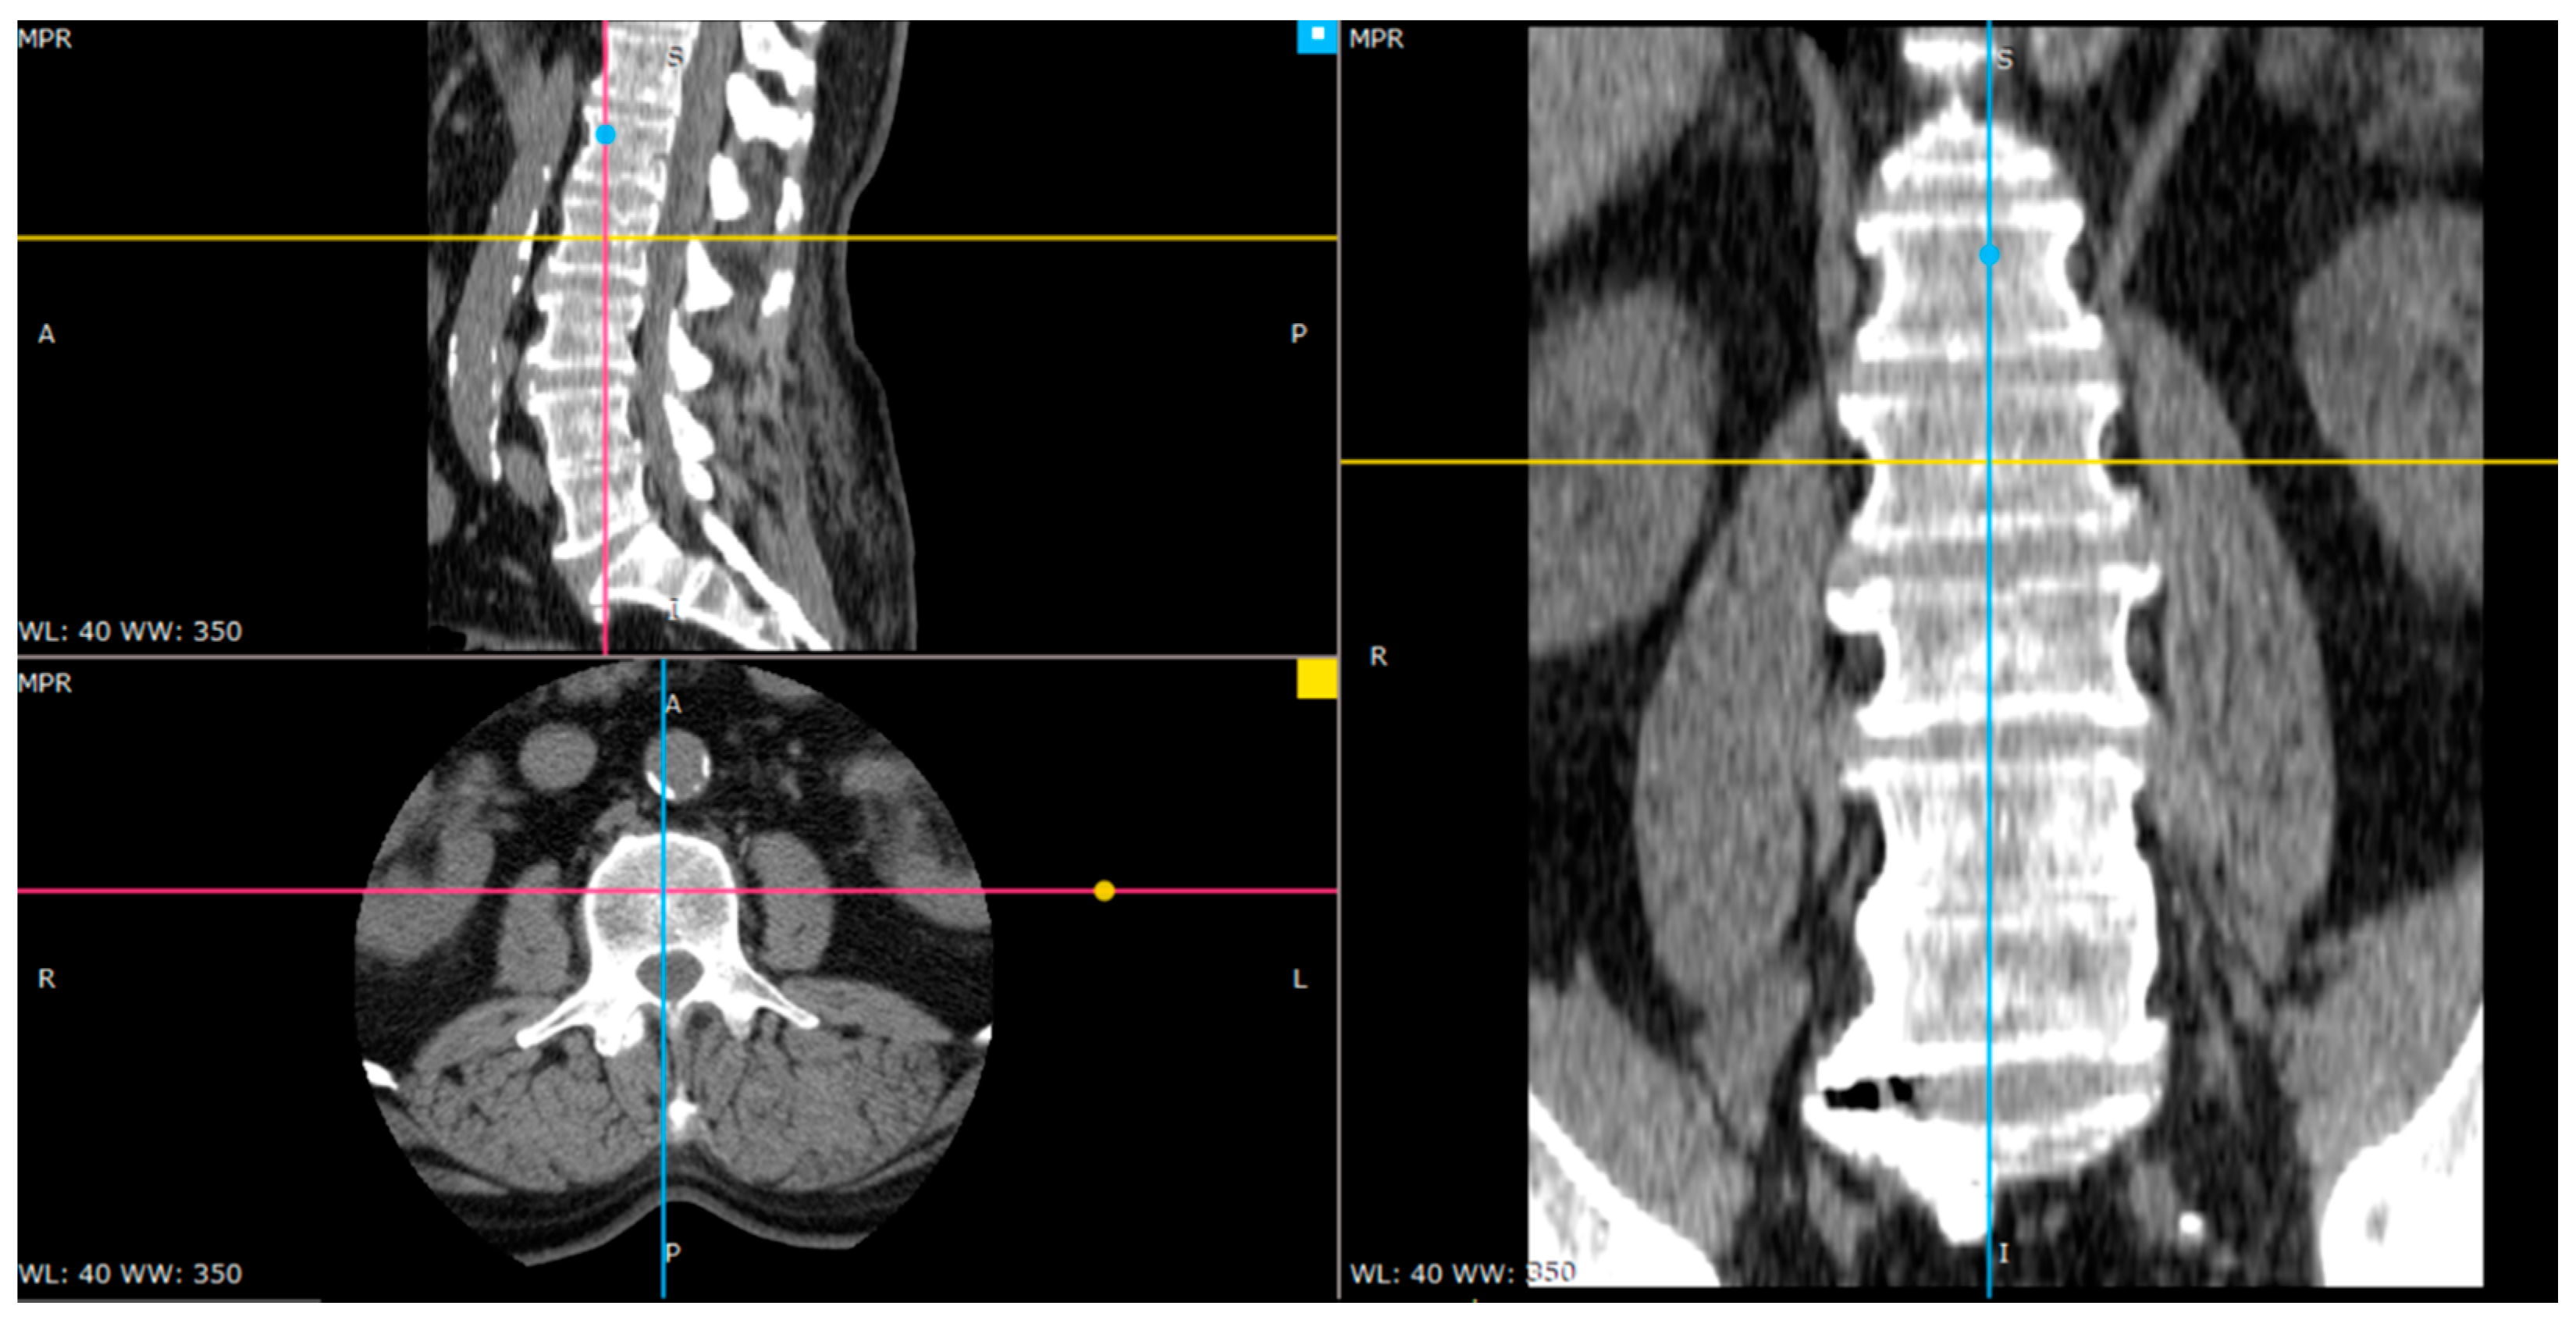

2.1. Material

2.2. Image Preprocessing